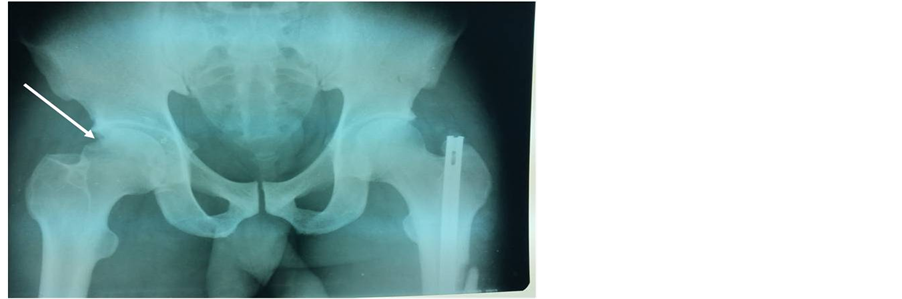

Plain X-rays confirmed a left subtrochanteric fracture and a right obturator dislocation of the hip with an intra-articular incarcerated fragment (Figure 3). Closed reduction of the dislocated hip and surgical treatment of the left subtrochanteric fracture by a Küntscher intramedullary nail; were performed the same day the patient was admitted. Post-reduction radiographs showed an articular gap widening with a defect in the superior lateral femoral head (Figure 4). A confirmation CT scan demonstrated an intra-articular incarcerated fragment (Figure 5). An arthroscopic extraction was warranted, but due to inadequate hospital equipment and patient financial hardship; the patient did not receive appropriate care. Fifteen months later; Mr. SA presented with a control X-ray showing early signs of coxarthrosis and peri-articular ossifications (Figure 6).

Figure 4. Anteroposterior X-ray of the pelvis showing an articular gap widening with a defect in the superior lateral femoral head (patient 3).